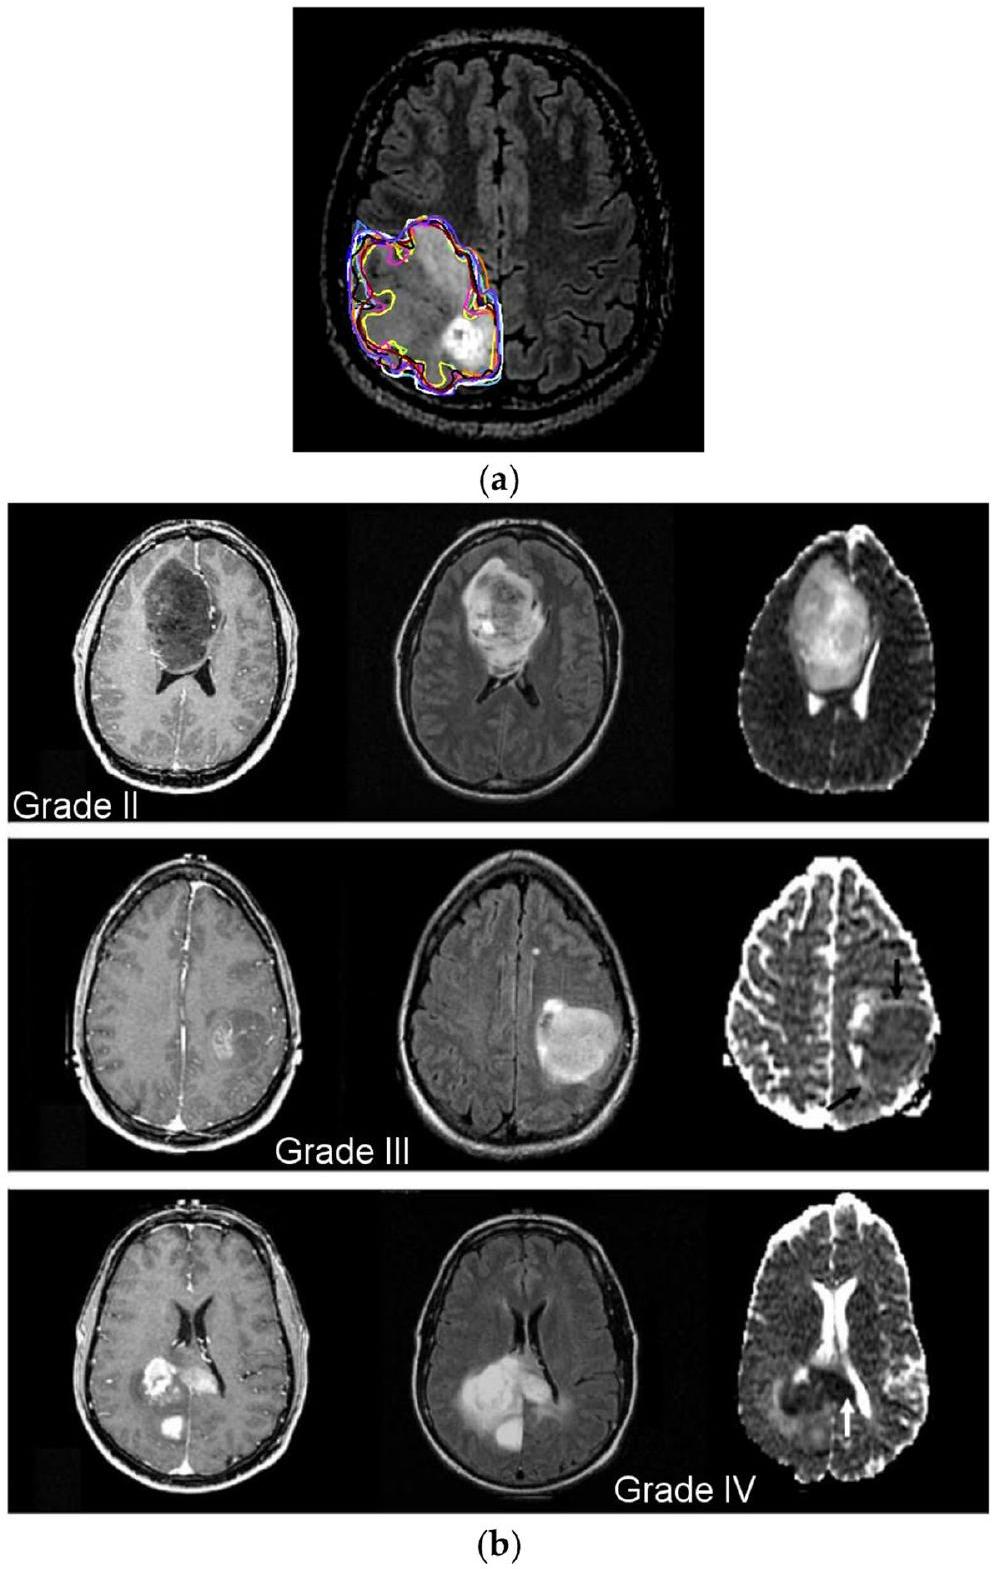

مجموعة بيانات أطلس جينوم السرطان للأورام الدبقية منخفضة الدرجة هي المجموعة الثالثة التي تم تحليلها (TCGA-LGG) [37]، وتحتوي على 242,185 صورة MRI لمرضى يعانون من أورام دبقية منخفضة الدرجة (G-I و G-II) وتدمج بيانات من 198 مريضًا. هذه المجموعات الثلاث هي جزء من مشروع أرشيف تصوير السرطان (TCIA) [38]. في كل حالة، تم إجراء تصوير متعدد الأنماط، بما في ذلك صور T1 المعززة بالتباين وصور FLAIR [39]. تتكون آخر مجموعة من البيانات المستخدمة في هذه الدراسة من 3067 صورة T1 محسنة بالتباين من 243 مريضًا يعانون من ثلاثة أنواع مختلفة من أورام الدماغ: الأورام الدبقية (1427 شريحة)، الأورام السحائية (709 شرائح)، وأورام الغدة النخامية (931 شريحة). الشكل 1 يوضح درجات مختلفة من أورام الدماغ من مجموعة البيانات. تم جمع 3165 صورة لنمط التصنيف-1، 1743 منها أورام خبيثة و1422 منها ليست كذلك. بالنسبة لنمط التصنيف-2، تم جمع 4195 صورة. هناك 910 صور طبيعية، 985 صورة أورام دبقية، 750 صورة أورام سحائية، 750 صورة أورام نخامية، و800 صورة ورم نقيل. بالنسبة لنمط التصنيف-3، نحصل على إجمالي 4720 صورة: 1712 G-II، 1296 G-III، و1712 G-IV. الجدول 1 يمثل تفاصيل تقسيم مجموعة البيانات للنموذج المقترح.

الشكل 1 أ تقسيم الورم يدويًا؛

The Cancer Genome Atlas Low-Grade Glioma dataset is the third dataset that was analyzed (TCGA-LGG) [37], and it has 242,185 MRI images of patients with low-grade gliomas (G-I and G-II) and incorporates data from 198 patients. These three datasets are part of the Cancer Imaging Archive (TCIA) project [38]. In each instance, multimodal imaging was performed, including T1-contrast-enhanced and FLAIR images [39]. The last collection of data used in this investigation consists of 3067 T1-weighted, contrast-improved images from 243 patients with three different types of brain tumors: gliomas ( 1427 slices), meningiomas ( 709 slices), and pituitary tumors ( 931 slices). Figure 1 depicts the different grades of brain tumors from the dataset. Totally, 3165 images are collected for the Classification-1 mode, 1743 of which are malignant tumors and 1422 of which are not. For the Classification-2 mode, 4195 images are collected. There are 910 normal images, 985 glioma images, 750 meningioma images, 750 pituitary images, and 800 metastatic images. For the Classification-3 mode, we obtain a total of 4720 images: 1712 G-II, 1296 G-III, and 1712 G-IV. Table 1 represents the dataset split-up details for the proposed model.

Fig. 1 a Manual tumor segmentation;